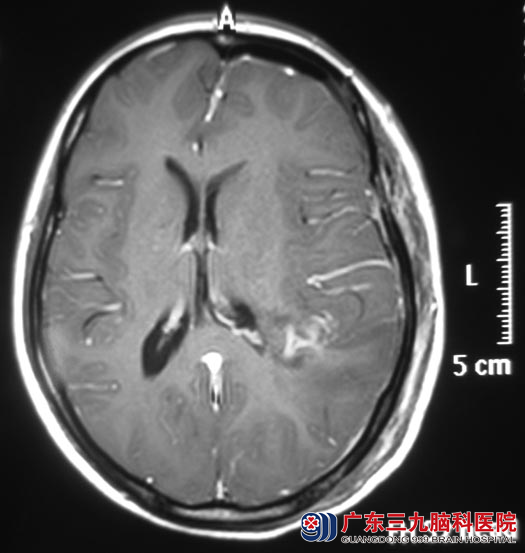

完善相关检查后,综合神经外科 鲁明主任主刀,在神经导航辅助下行左侧额顶叶肿瘤切除术。术中见皮层下肿瘤呈胶冻状,质软,血供丰富,连同皮层病变脑组织及肿瘤组织在显微镜下全切,过程顺利。http://www.999brain.com/

术后陈女士头痛、肢体乏力症状明显改善。病理结果为:间变型星形细胞瘤。

▲手术后